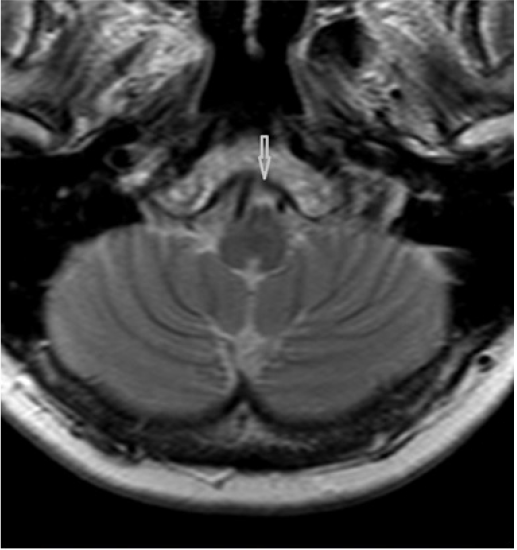

Native cerebral magnetic resonance imaging examination has revealed four features: normal MR signal of the brainstem; dominant and sinuous right vertebral artery (VA) compressing junction between medulla oblongata and spinal cord; medulla oblongata clamping in between the two vertebral arteries; and loss of foramen magnum cerebrospinal fluid (CSF) spaces due to low lying cerebellar tonsils tips, while cisterna magna is still visible. Figure 1 depicts the VA compressing right ventrolateral junction of medulla oblongata with spinal cord. Figure 2 reveals the medulla clamping in between the two vertebral arteries.

According to our knowledge, this is the first reported case of HAS due to a dilated or sinuous VA. A sinuous VA compressing the medulla oblongata – spinal cord junction may compress the VRG which contains both inspiratory and expiratory neurons, as well as neurons which control larynx and pharynx muscles.